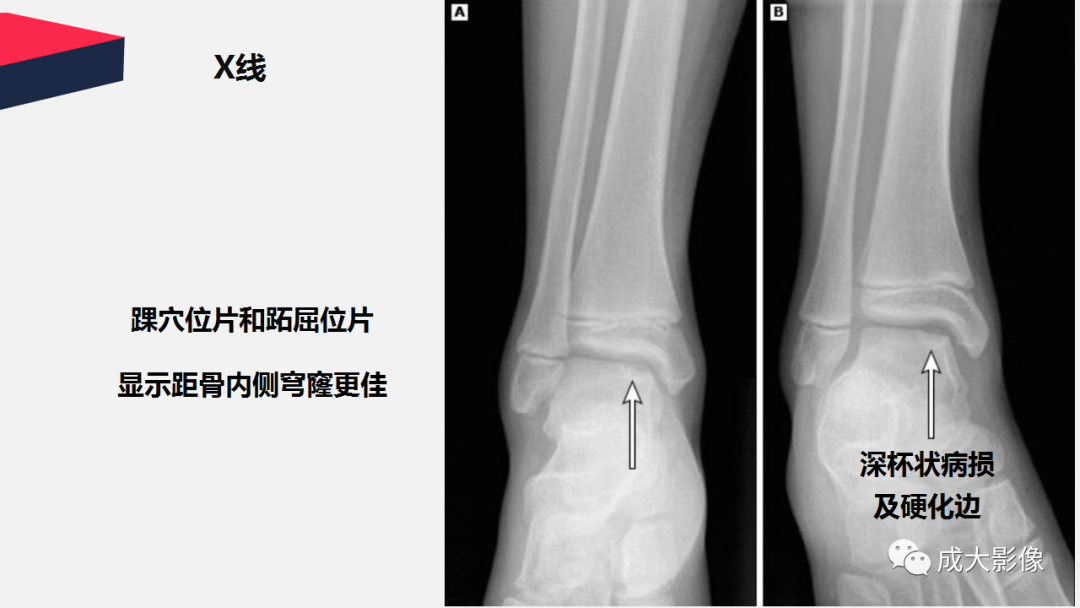

【PPT】剥脱性骨软骨炎